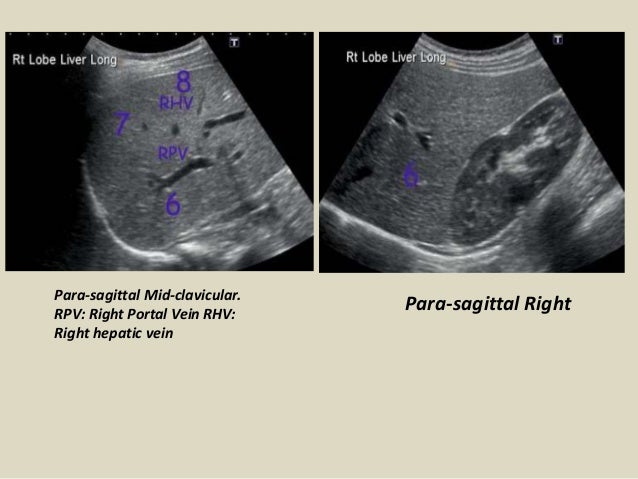

Ultrasound evaluation of normal fetal anatomy. Liver ultrasound showing education liver segments normal liver anatomy portal vein hepatic veins the biliary tree and ultrasound scanning protocol worksheets.